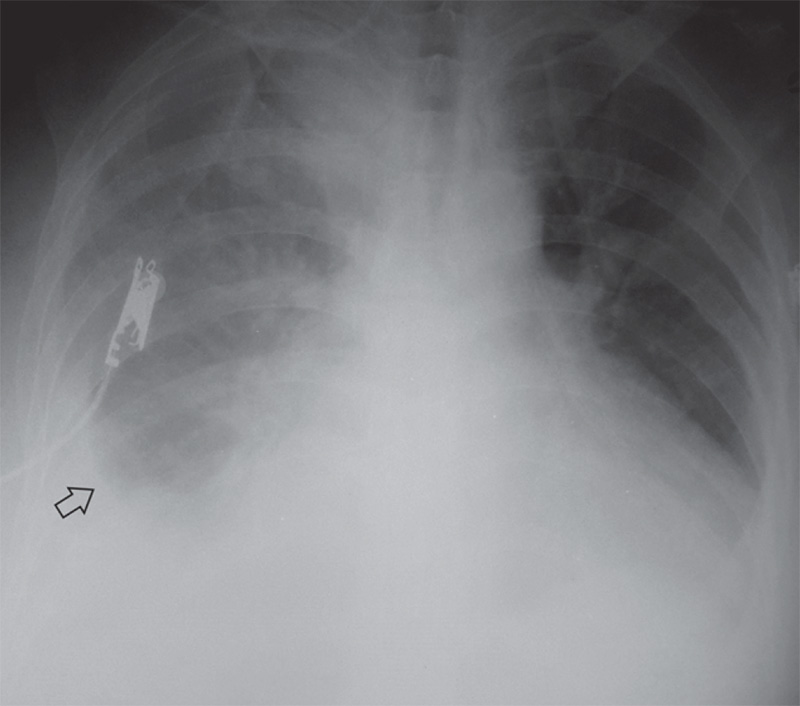

При проведении рентгенографии в положении пациента лежа, наблюдается другая рентгенологическая картина – отмечается снижение прозрачности легочного поля, на фоне которого определяется легочный рисунок (см рисунок 8), что обусловлено более равномерным распределением жидкости вдоль легкого в горизонтальном положении. При этом синусы могут визуализироваться как свободные или затененные, а купол диафрагмы становится нечетким. На рентгенограмме, выполненной в положении пациента лежа, можно обнаружить плевральный выпот в количестве 500-1000 мл, а небольшие объемы жидкости в плевральной полости могут не определяться.

Рисунок 8. Гидроторакс слева (рентгенограмма, выполненная в положении пациента лежа): отмечается снижение прозрачности левого легочного поля, обусловленное наличием выпота в плевральной полости (на этом фоне визуализируется легочный рисунок). В проекции трахеи определяется тень трахеостомической трубки

В случае накопления в плевральной полости большого количества жидкости, затемнение становится высокоинтенсивным, легочный рисунок не определяется (рисунок 9).

Рисунок 9. Правосторонний гидроторакс (рентгенограмма, выполненная в положении пациента лежа): отмечается снижение прозрачности правого легочного поля, обусловленное наличием выпота в плевральной полости. В среднем и верхнем отделах легочного поля можно определить легочный рисунок, в нижнем отделе легочного поля отмечается высокоинтенсивное снижение прозрачности. В нижнем отделе определяется относительно четкая граница выпота (см стрелка), синус справа не дифференцируется

Необходимо помнить, что одностороннее снижении прозрачности легочного поле может быть обусловлено несимметричной укладкой больного при проведении рентгенографии (особенно в условиях отделения интенсивной терапии). Нужно всегда брать во внимание симметричность укладки больного, ориентируясь на расстояния от стернальных концов ключиц до остистых отростков грудных позвонков (это расстояние должно быть примерно одинаковым с обеих сторон). В случае ассиметричной укладки снижение прозрачности определяется не только в легочном поле, также повышается интенсивность затенения мягки тканей на этой же стороне. В случае возникновения сомнения при постановке диагноза, следует выполнить УЗИ, что позволит определить наличие жидкости в плевральной полости, даже в положении лежа.